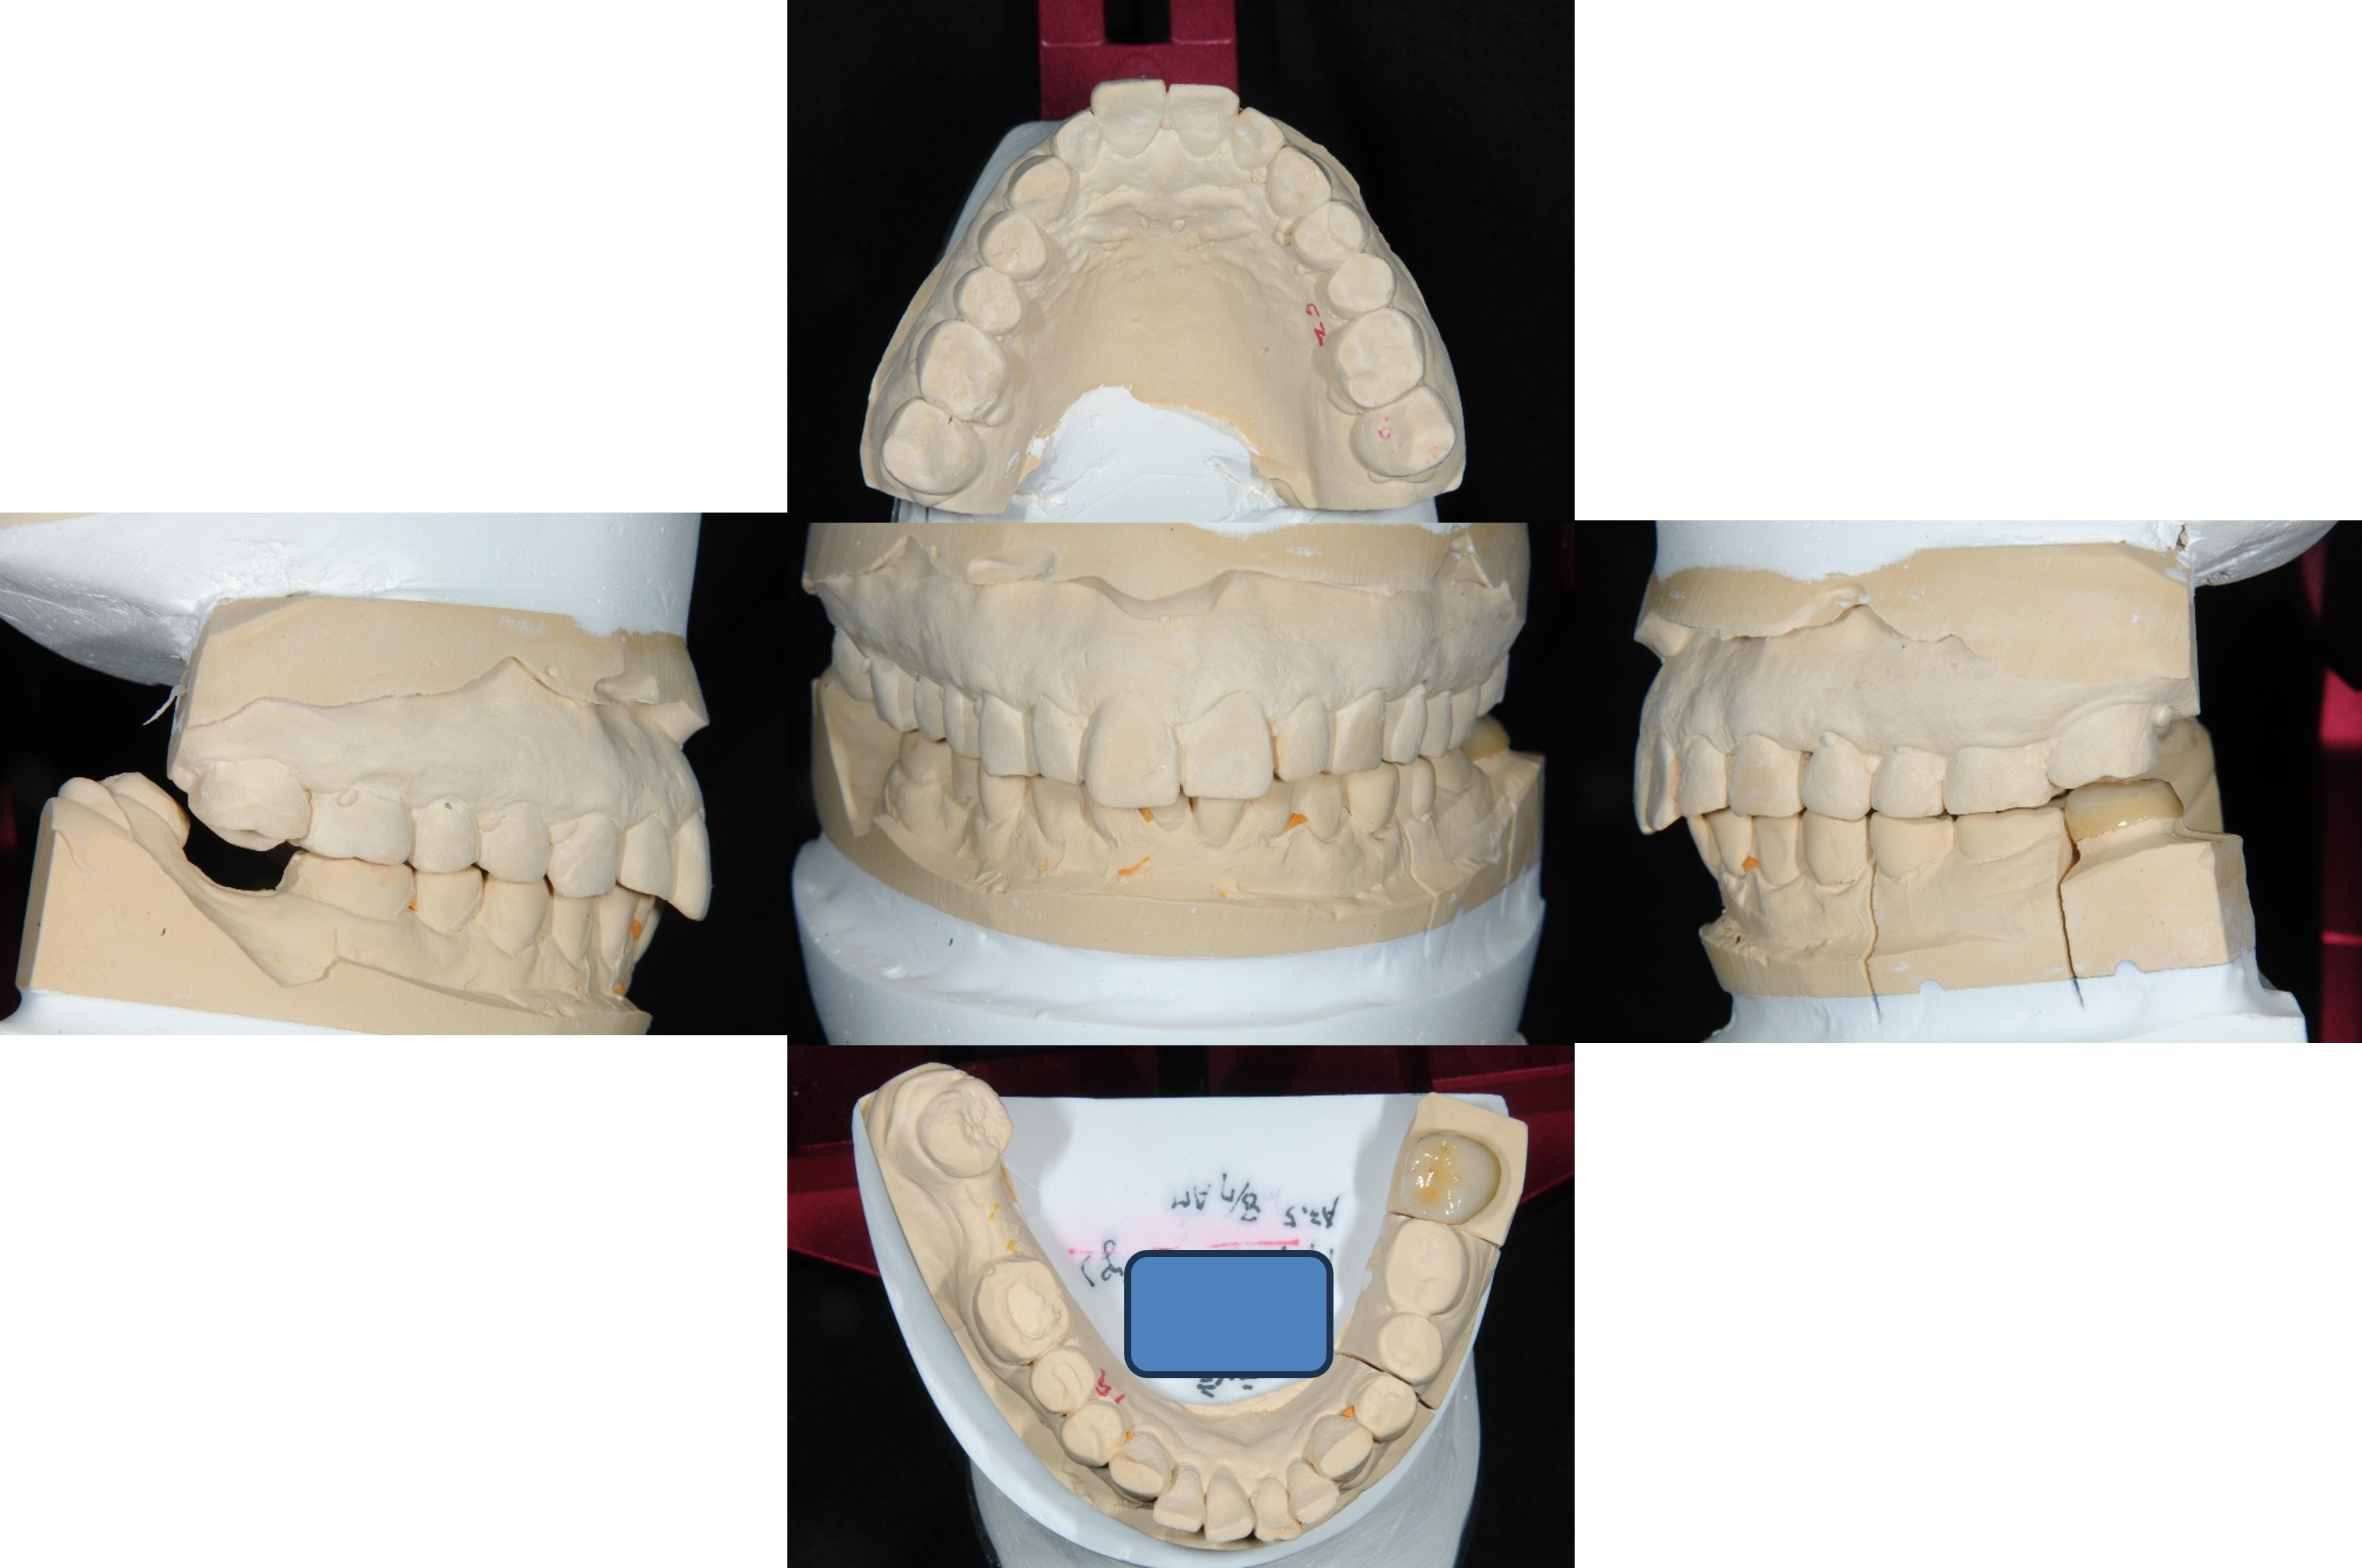

上面弓、上咬合器

技師於咬合器製作全瓷冠